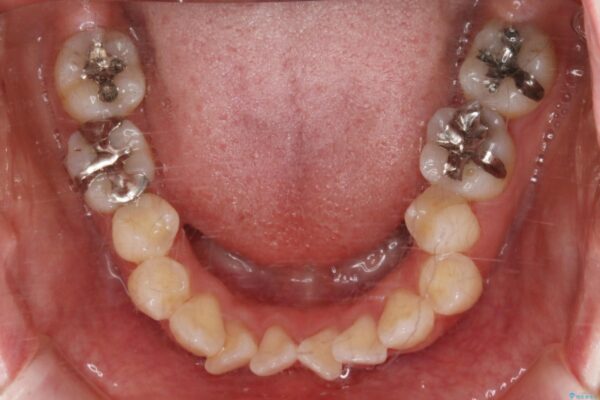

治療計画

お仕事柄、目立たない矯正装置をご希望されたため、今回はインビザラインと抜歯を組み合わせた治療で対応します。

抜歯後の大きなスペースの管理は通常ワイヤー矯正が得意ですが、こちらの患者様は奥歯の噛み合わせが比較的安定しており、犬歯の傾きを改善すれば良いため、マウスピースでも十分に精密な治療が可能と判断しました。

抜歯矯正

歯のガタつきの度合いが強い場合や、上下で大きく噛み合わせがズレている時などに、その改善のための大きなスペースを作る代表的手段が「抜歯」です。

一般的には第一小臼歯(犬歯の一つ隣の歯)を抜くことが多く、前歯のガタつきを改善したり口元を引っ込める場合に利用されます。